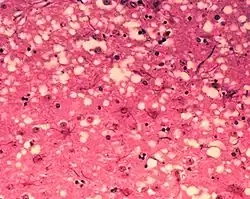

![]() Гистологический препарат — ткань лобной доли головного мозга больного болезнью Крейтцфельдта — Якоба | |

Прионы вызывают нейродегенеративные заболевания, так как образуют внеклеточные скопления в центральной нервной системе и формируют амилоидные бляшки, которые разрушают нормальную структуру ткани. Разрушение характеризуется образованием «дыр» (полостей) в ткани, и ткань принимает губчатую структуру из-за формирования вакуолей в нейронах[68]. Другие наблюдаемые при этом гистологические изменения — астроглиоз (увеличение численности астроцитов из-за разрушения близлежащих нейронов) и отсутствие воспалительных реакций[69]. Хотя инкубационный период прионных заболеваний, как правило, очень долог, после появления симптомов болезнь прогрессирует быстро, приводя к разрушению мозга и смерти[70]. Проявляющимися при этом нейродегенеративными симптомами могут быть конвульсии, деменция, атаксия (расстройство координации движений), поведенческие и личностные изменения.